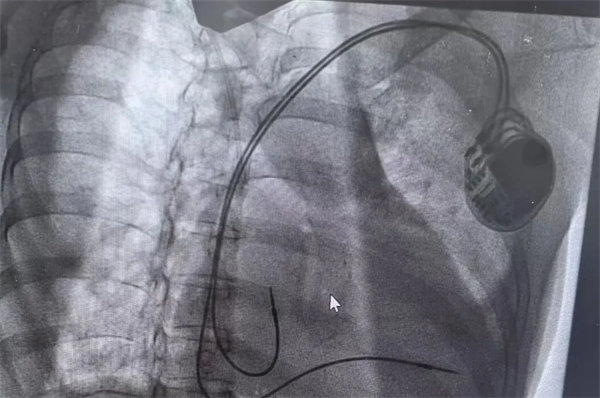

高級生命支持穩住病情

患者轉入重癥醫學科心電監護提示間歇性三度房室傳導阻滯、室性心動過速,同時合并心源性休克。心血管內一科陳萬林副主任醫師急會診后考慮三度房室傳導阻滯是患者發生意識喪失的元兇。立即行床旁臨時起搏器植入術,快速植入臨時起搏器后患者再未出現惡性心律失常。

在充分術前準備和家屬的理解支持下,心血管內一科主任翟向偉副主任醫師、陳萬林副主任醫師及介入導管室團隊為患者實施了雙腔心臟永久性起搏器植入術。通過左側腋靜脈入路,精準、輕柔操作順利植入起搏器。術后經過醫護團隊的精細診治,起搏器囊袋如期愈合,患者可自由活動,生活質量得到有效改善?;颊呒凹覍俾冻隽司眠`的笑容。